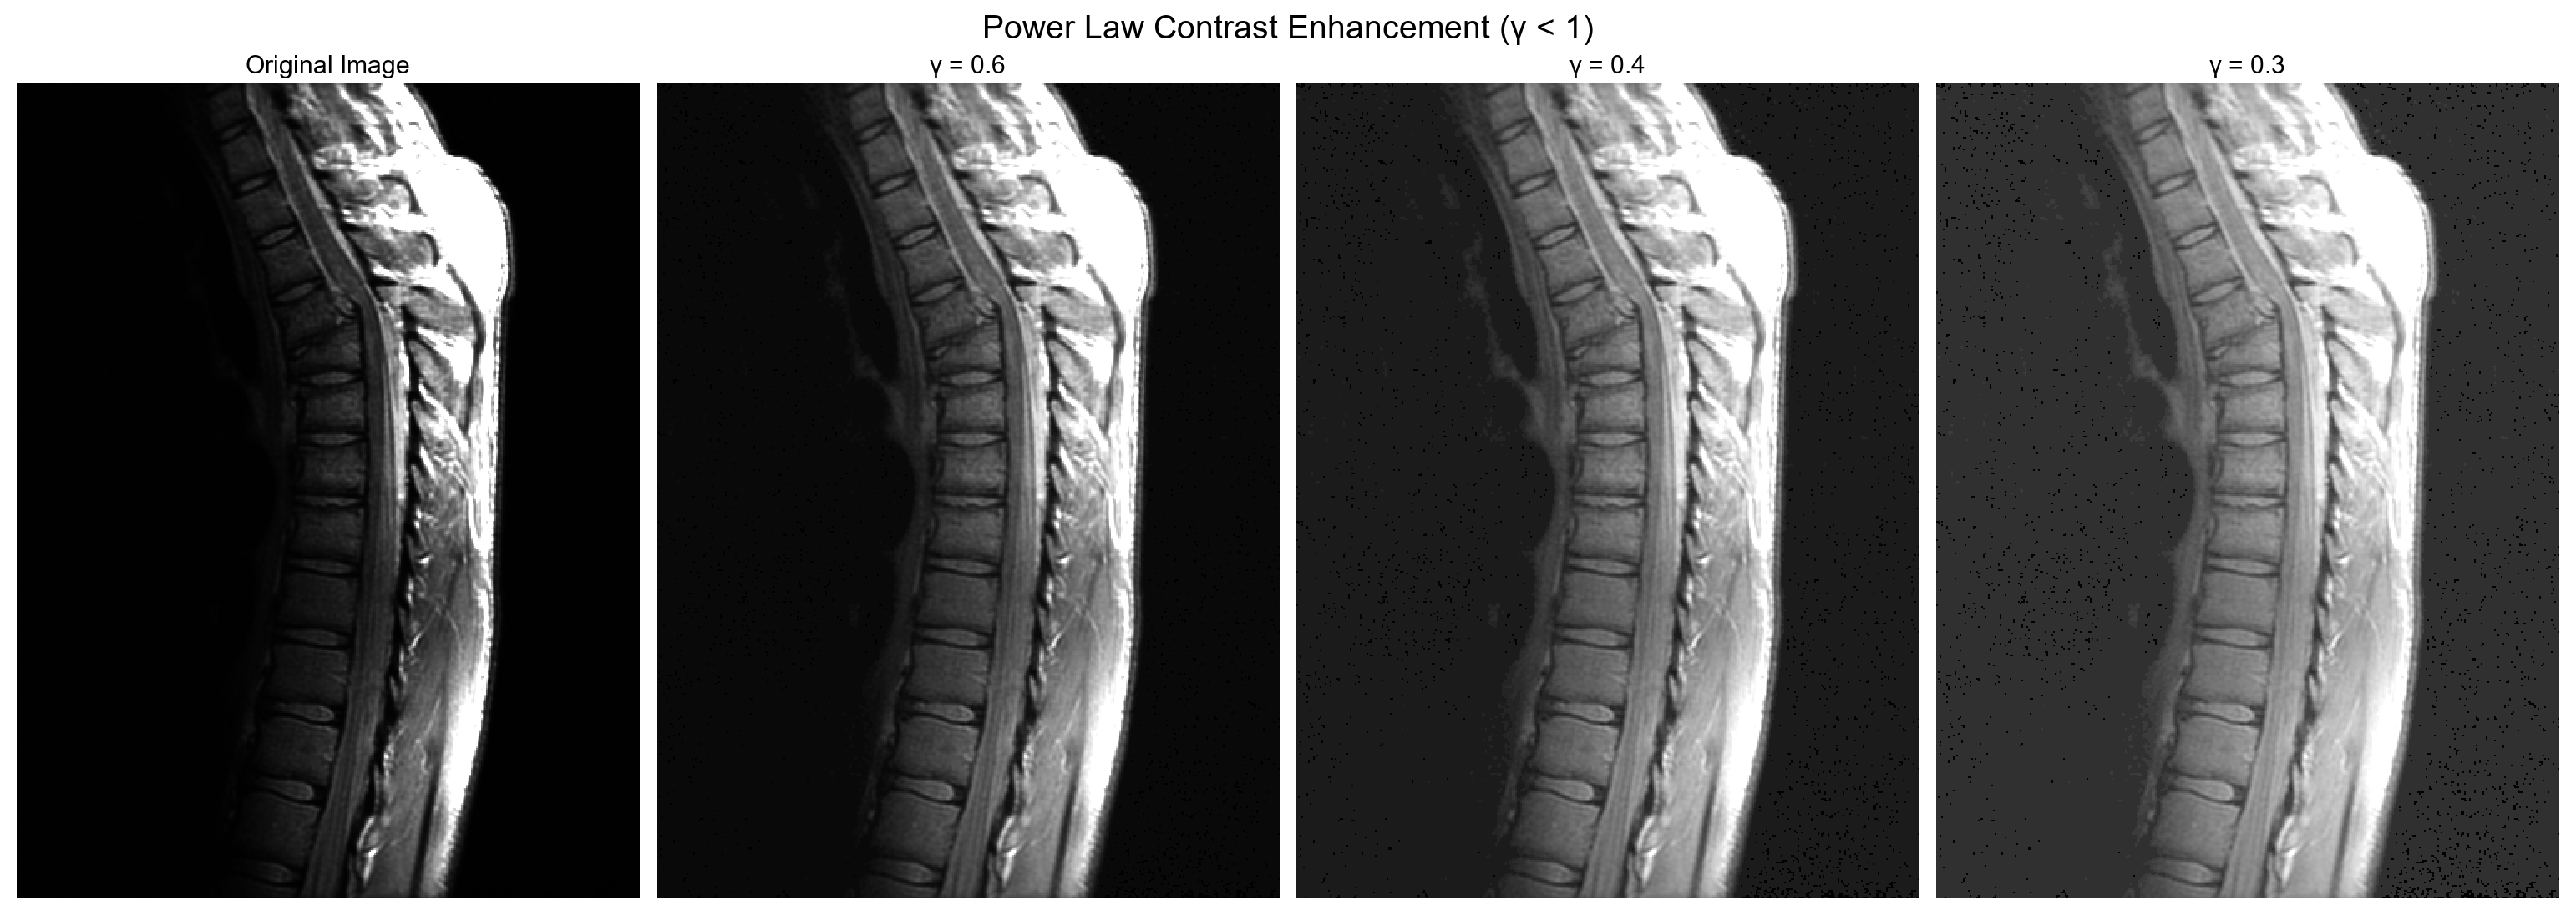

def gammaTransform(gamma, original_array):

c_gamma = 255 / np.power(np.max(original_array), gamma)

gamma_array = c_gamma * np.power(original_array, gamma)

gamma_array = gamma_array.astype(np.uint8)

return gamma_array

PowerLow(γ < 1)는 전체적으로 이미지를 부드럽게 하면서도 중요한 영역의 시각적인 구분을 명확하게 하는데 도움.

파워 로 변환은 어두운 부분의 디테일을 살려주면서 밝은 부분도 디테일이 살아있음. 전반적으로 대비를 더욱 증가시켜줍니다.